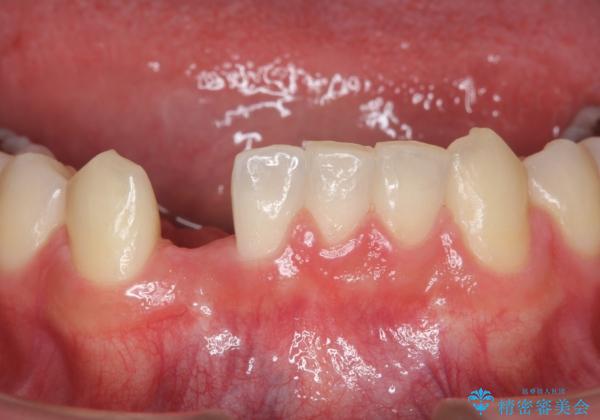

唇側の骨増成もしっかり行い、前歯部インプラントによくある、歯茎が下がって見えることもない、審美的なインプラント補綴ができました。